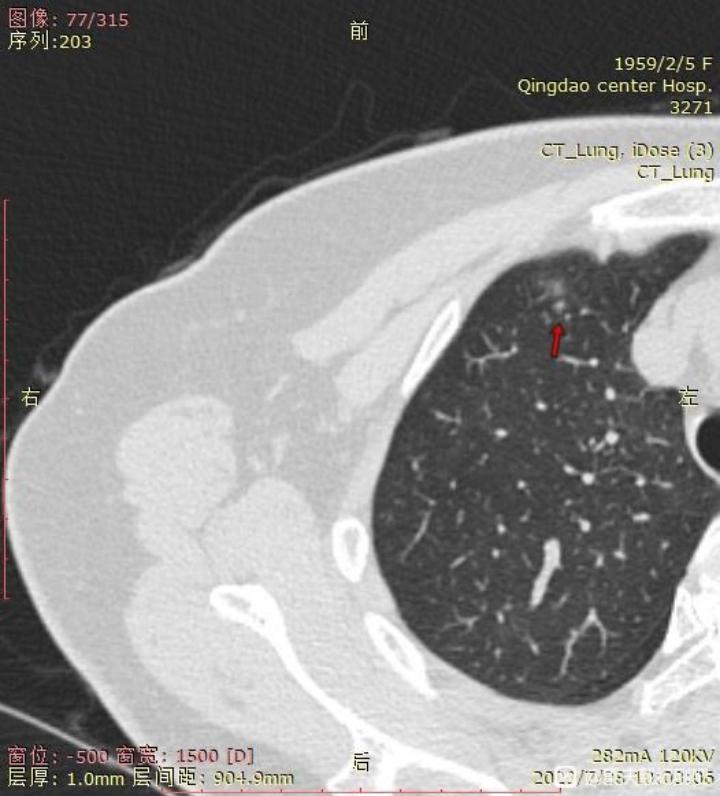

右肺未切除结节截图:

1. 右肺上的小结节是哪一种类型,如果真不好的话,消融可以吗?毕竟刚手术完,无法近期再手术。